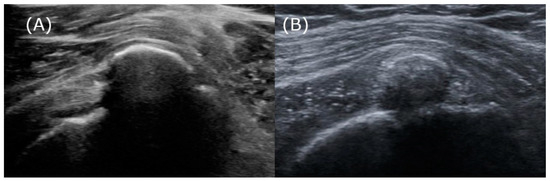

Another plausible explanation, beyond the inaccuracies inherent in qualitative radiographic analysis, is that ultrasound attenuation is not solely determined by the stage of calcification but may also vary due to physical interactions with neighboring structures. Specifically, in confirmed cases of the resorption phase, where calcifications have been successfully removed via barbotage, the calcifications exhibit arc-shaped attenuation and produce acoustic shadows (Figure 7). The authors observed a commonality among these cases: these calcific deposits were densely packed within a confined space limited by the surrounding tendons and bursal wall. Such densely packed deposits could create significant density differences that reflect ultrasonic waves, resulting in arc-shaped attenuation from above and accompanying acoustic shadows. Therefore, it seems that relying solely on attenuation to determine the stages of calcification appears to have its limitations.

Figure 7.

The resorptive phase calcifications, which exhibit arc-shaped attenuation and acoustic shadows beneath the bursal wall. (A) A 49-year-old female patient demonstrates calcification with pronounced arc-shaped attenuation and clear acoustic shadows. (B) A 40-year-old female patient exhibits arc-shaped attenuation with partial ultrasound penetration, allowing limited observation of the inner structure’s upper portion. The acoustic shadow is partially faint, providing a faint view of the humeral cortex.